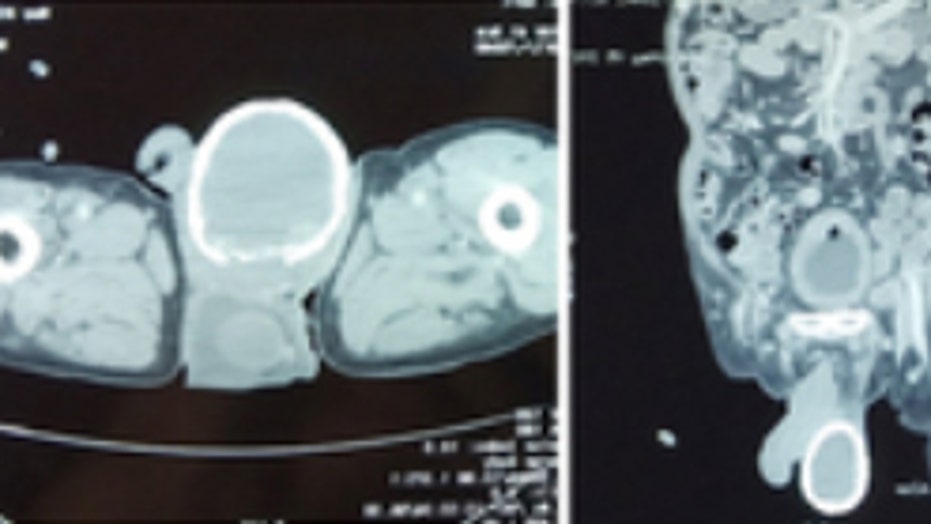

A fluid-filled sac had formed around the man's testicle and began to calcify. (BMJ Case Reports)

The 80-year-old's testicle appeared swollen and calcified. The man, who was not identified, was diagnosed with lymphatic filariasis, which caused a fluid-filled sac caused a hydrocele to form around his testicle that then began to calcify, according to LiveScience.